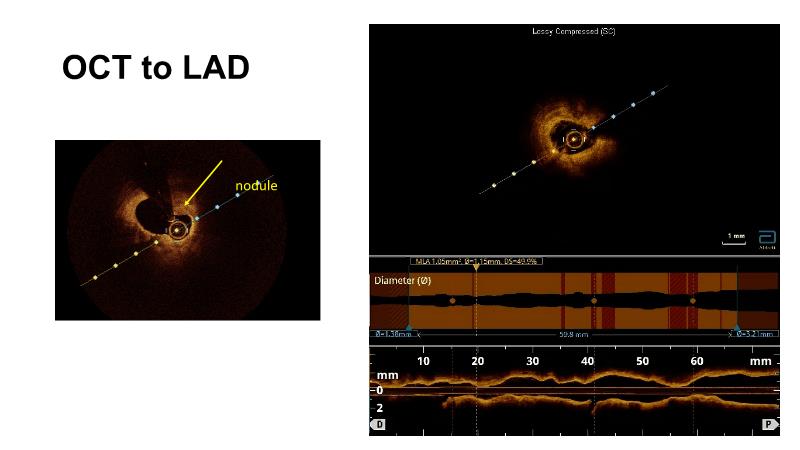

Optimal PCI in patient with long calcified lesion

In this session, follow a LIVE case from the Chest Diseases Hospital in Kuwait and learn what the best strategy is to treat patients who present with a very long calcified coronary artery lesion, as well as how to select the best device and which different types of stents can be used.

- To learn correct interpretation of a long-calcified lesion and how to adopt procedural strategy

- To understand value of intracoronary imaging in patient treatment